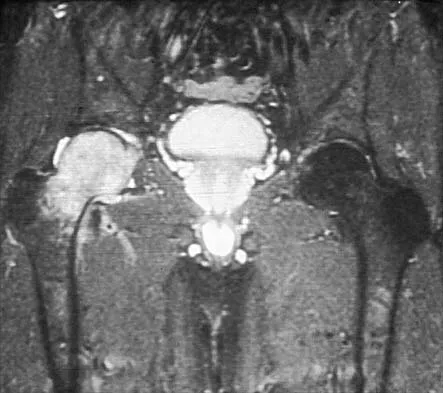

Figures 10a through 10c show the plain radiograph and MRI scans of a 41-year-old man who has right hip pain. What is the most likely diagnosis?

Explanation

Transient osteoporosis is a self-limited painful but reversible disorder. Although first described in pregnant women, it is more common in young to middle-aged men. The radiograph shows loss of mineralization in the right hip relative to the left side. There is no osseous destruction or cortical expansion typical of metastasis or giant cell tumor. The process is confined to the femoral side of the joint unlike rheumatoid arthritis, which would be centered in the joint. Osteonecrosis is better defined with sharp but irregularly shaped margins, and there is no double-line sign. The MRI scans reveal diffuse edema in the femoral head and neck that is atypical for osteonecrosis. Transient osteoporosis may recur in the same or opposite hip.